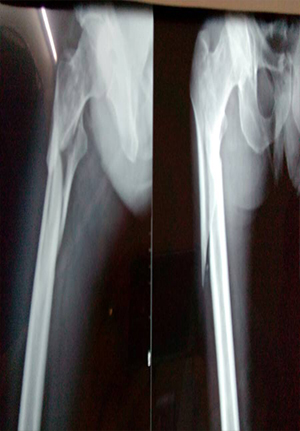

Proximal femoral nail for comminuated subtrochanteric fracture